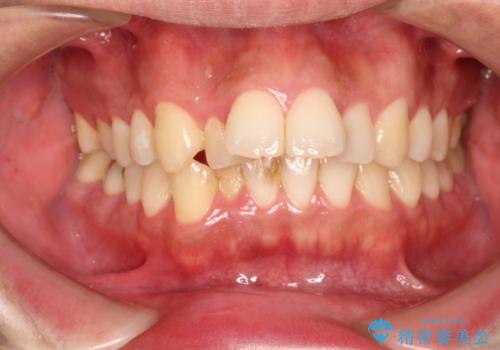

出っ歯の抜歯矯正 裏側ワイヤーによる目立たない矯正

- 出っ歯が気になるとのことで来院されました。

上顎の前から4番目の歯を両側、合計2本抜歯して矯正する計画としました。

目立たない装置がご希望でしたので、上下裏側ワイヤー装置を選択されました。